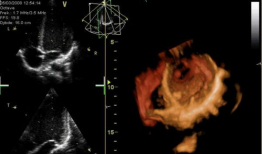

心脏跳动的视频,揭秘心脏跳动的奥秘

你知道吗?最近在网上流传着一个特别神奇的视频,它记录了心脏跳动的瞬间。这可不是普通的视频,它让我们仿佛能感受到心跳的力量,那种感...